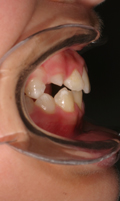

.... griglia linguale ( solo 4 mesi) e successivamente con Barra palatale in intrusione (discostata dal palato),in contemporanea al dispositivo elastodontico. Sono state associate sedute di terapia miofunzionale logopedica. Il caso e' ancora sotto controllo ma la durata di trattamento effettiva e' stata di anni 2!.